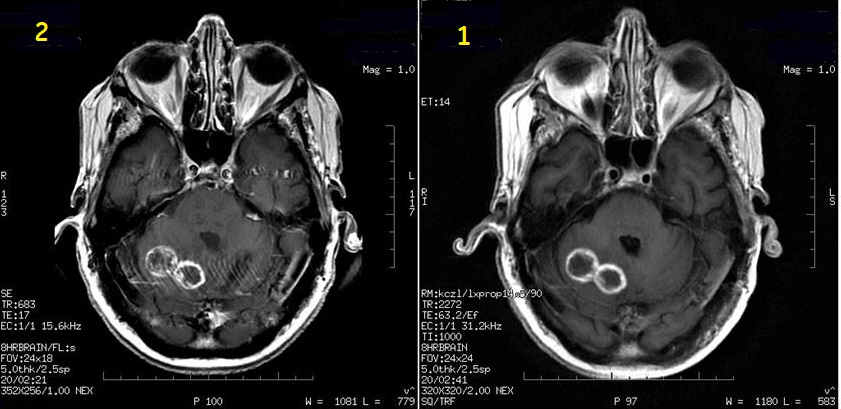

Figure 4. Frequency A/P and S/I localizer comparison

Table 4. Image legend

NumberDescription

1Frequency A/P in localizer

2Frequency S/I in localize